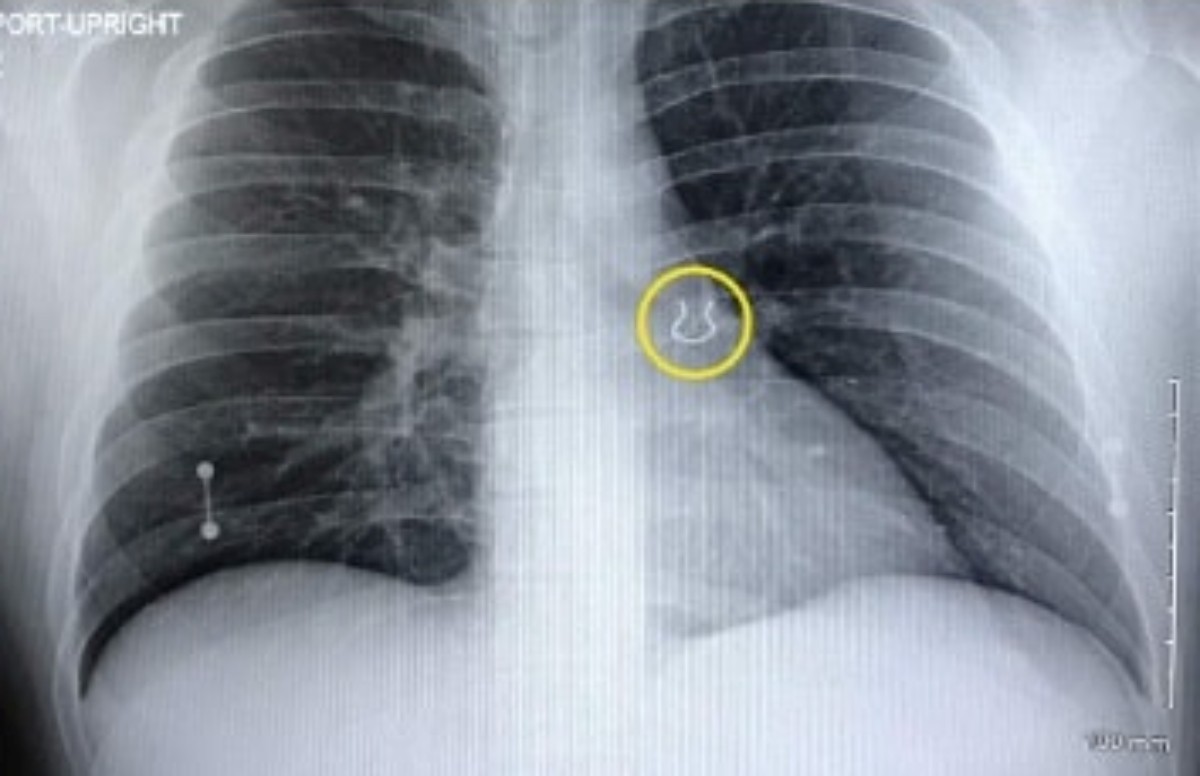

Την επόμενη μέρα πήγε στο νοσοκομείο για εξετάσεις και η ακτινογραφία αποκάλυψε κάτι ασυνήθιστο στον άνω λοβό του αριστερού πνεύμονα. Ο γιατρός του έδειξε τη σάρωση και το μικρό, αντικείμενο τον άφησε άναυδο.

Ήταν το σκουλαρίκι μύτης που είχε χάσει πριν από χρόνια και που ποτέ δεν θα περίμενε να βρει στον πνεύμονά του

«Ο γιατρός ήρθε και μου έδειξε την εικόνα της ακτινογραφίας και μου είπε: Σας φαίνεται γνωστό αυτό;». θυμήθηκε ο Joey Lykins. «Έλεγα: Πλάκα μου κάνετε! Το έψαχνα αυτό. Δεν ήξερα τι συνέβαινε, αλλά ποτέ δεν θα πίστευα ότι ήταν αυτό».

Κάποια στιγμή, ο Lykins σκέφτηκε ότι μπορεί να κατάπιε κατά λάθος το δαχτυλίδι, αλλά ποτέ δεν φαντάστηκε ότι θα μπορούσε να το εισπνεύσει. Αλλά τελικά το έκανε. Ο 35χρονος υπολογίζει ότι το σκουλαρίκι στη μύτη έπεσε ενώ κοιμόταν, ταξίδεψε στην τραχεία του και κόλλησε στον αριστερό του πνεύμονα.

«Δεν ξέρω αν θα μπορούσε να προκαλέσει ζημιά, αλλά ήταν τυλιγμένο σε ουλώδη ιστό, οπότε δεν φαινόταν να πηγαίνει πουθενά», δήλωσε ο Lykins, ο οποίος έχει άλλα 12 piercing.